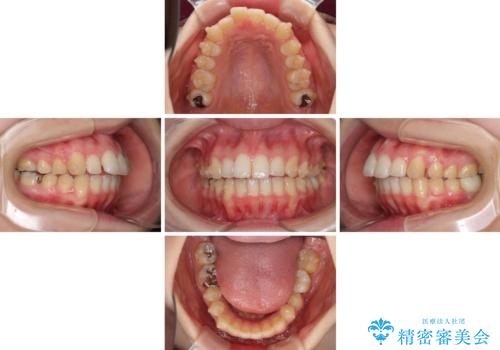

- 口の閉じにくさと割れてしまった奥歯を気にして来院された患者様です。

IPR(歯と歯の間を削る)と歯列全体の後方移動によって口元が引っ込むように設計し、インビザラインにより治療を行うこととしました。

割れてしまった奥歯は抜歯し、矯正治療中の良いタイミングでインプラントを埋入することとしました。

インプラントは、治療期間を短くすることが可能な、ストローマン社のSLActiveを使用することとしました。

上下正中がずれていたため、抜歯による矯正治療も検討しましたが、口元がそれほど突出していなかったため、非抜歯にて矯正することになりました。

その結果正中のズレは残りましたが、口を閉じたときの感覚や奥歯の咬み合わせには全く問題なく、患者様には大変満足していただきました。